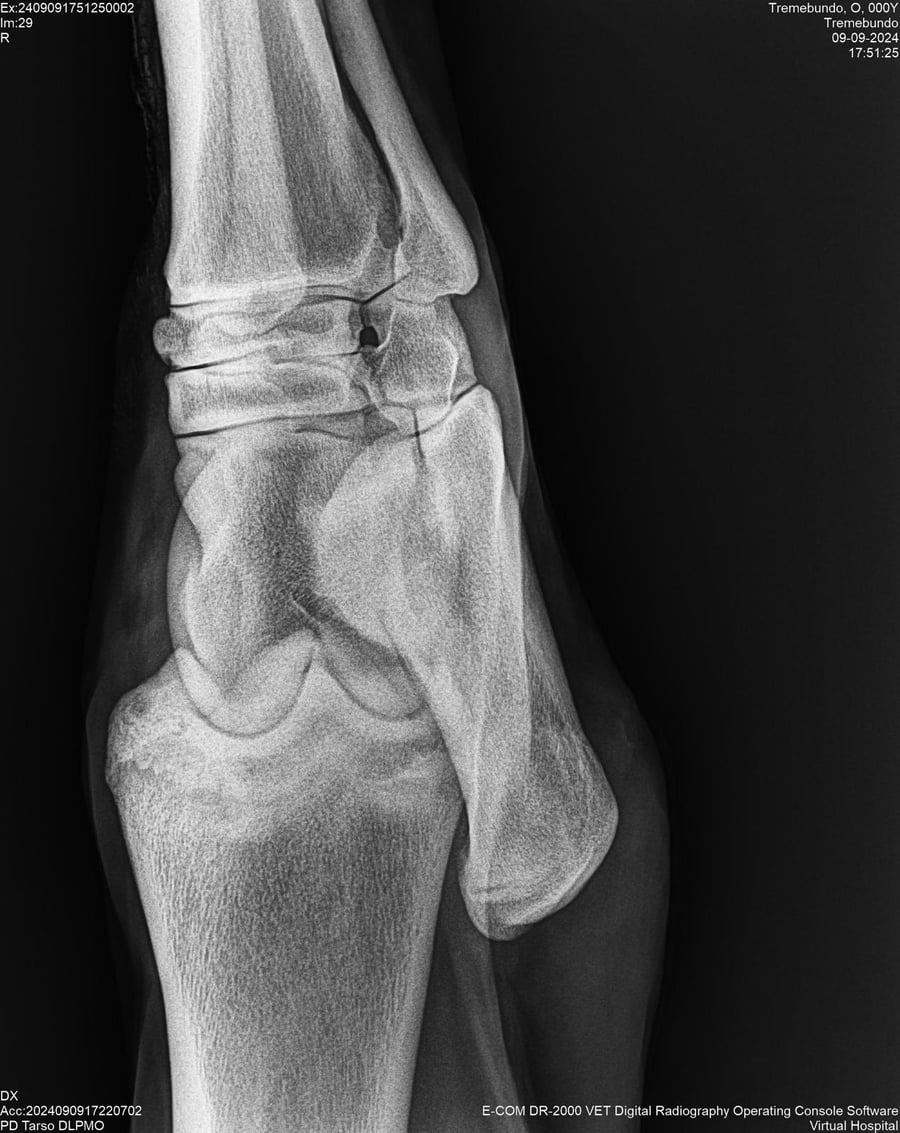

LOTE 37, TREMEBUNDO

Identificador: #291140-

Generacion 2022